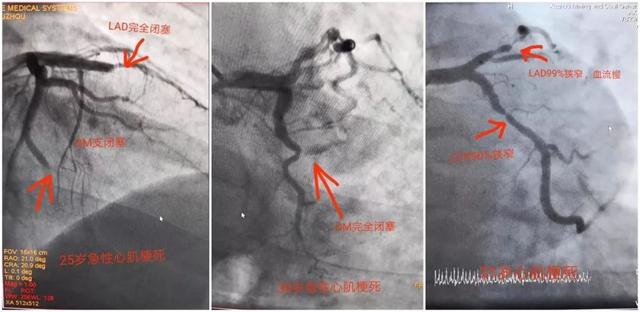

强烈的胸口疼痛,大汗,并有濒死感,这让小甲开始感觉不安。急诊为小甲行冠状动脉造影检查。经过检查,小甲的前降支和回旋支都已经完全的堵塞,随即医生为他进行了血运重建。

“人体有三支冠状动脉,三根堵塞了两根,小甲的心梗属于相当严重的,心肌细胞坏死较多,梗死面积大。而且心肌细胞一旦坏死,会出现不可逆的损伤”,刁军主任介绍说,小甲如果早一点到医院进行专业检查,就不会发生这么严重的心梗了。